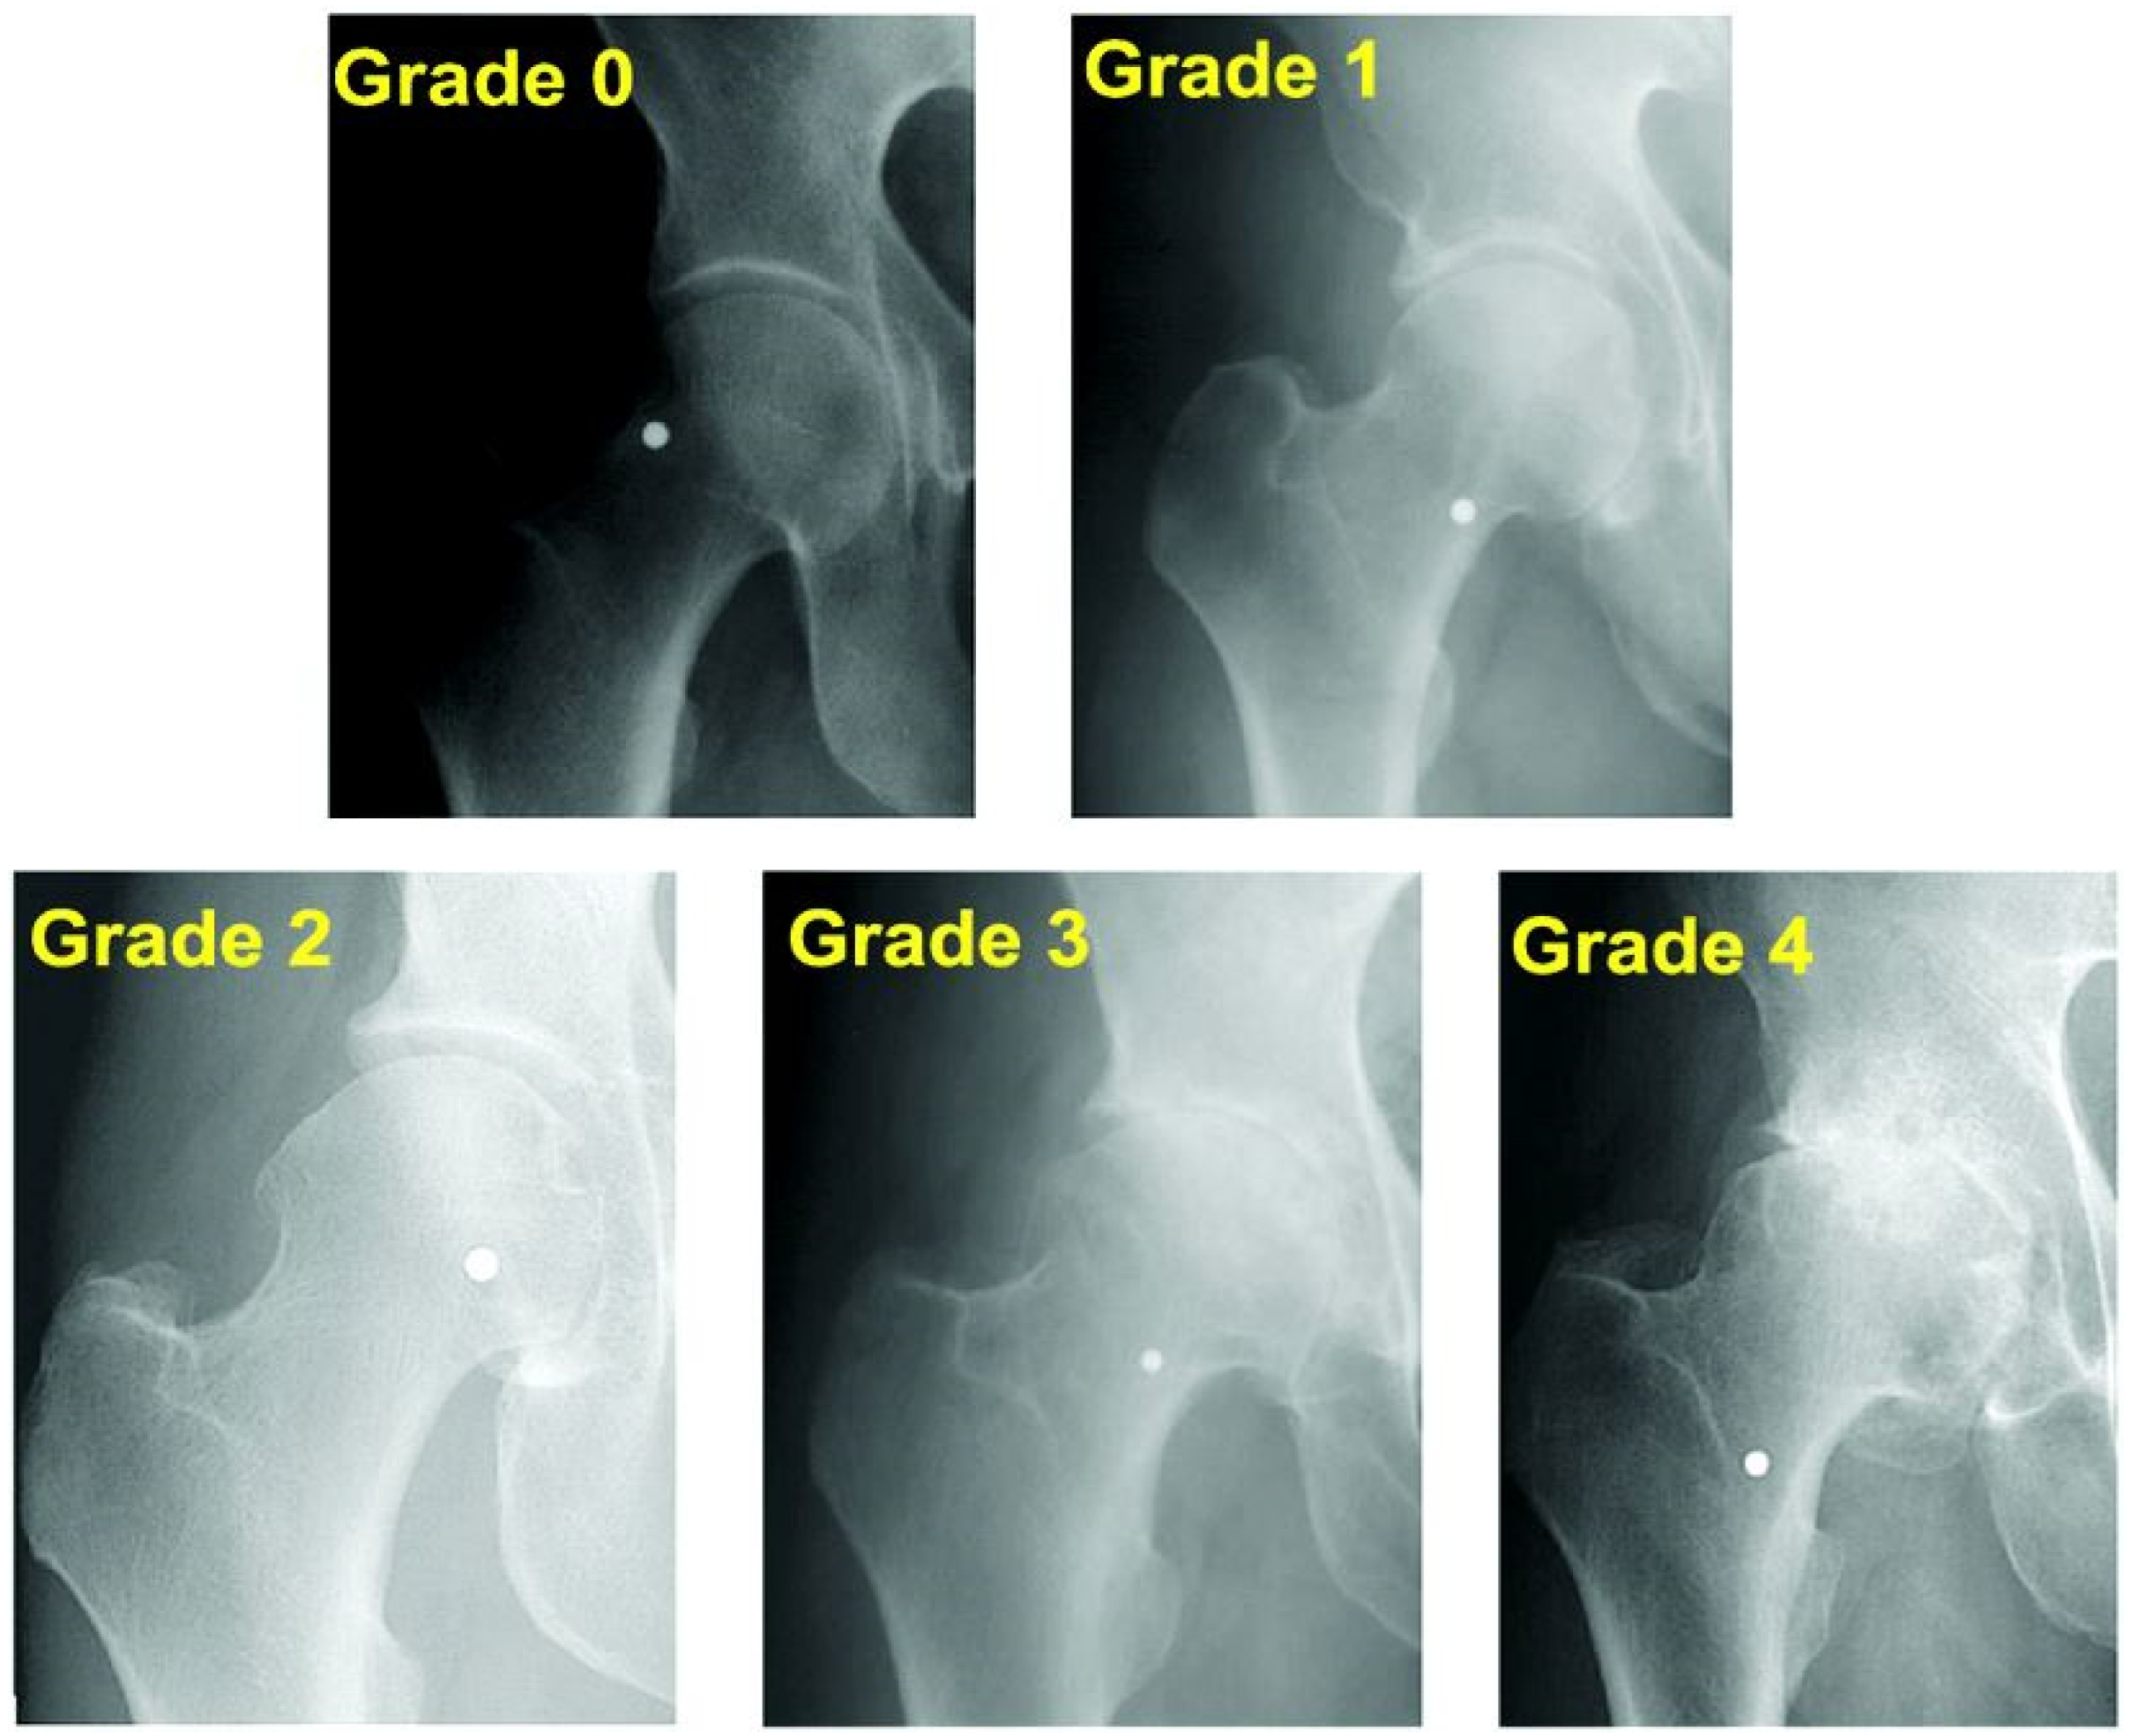

- Kohn, M.D.; Sassoon, A.A.; Fernando, N.D. Classifications in Brief: Kellgren-Lawrence Classification of Osteoarthritis. Clin. Orthop. Relat. Res. 2016, 474, 1886–1893. [Google Scholar] [CrossRef]